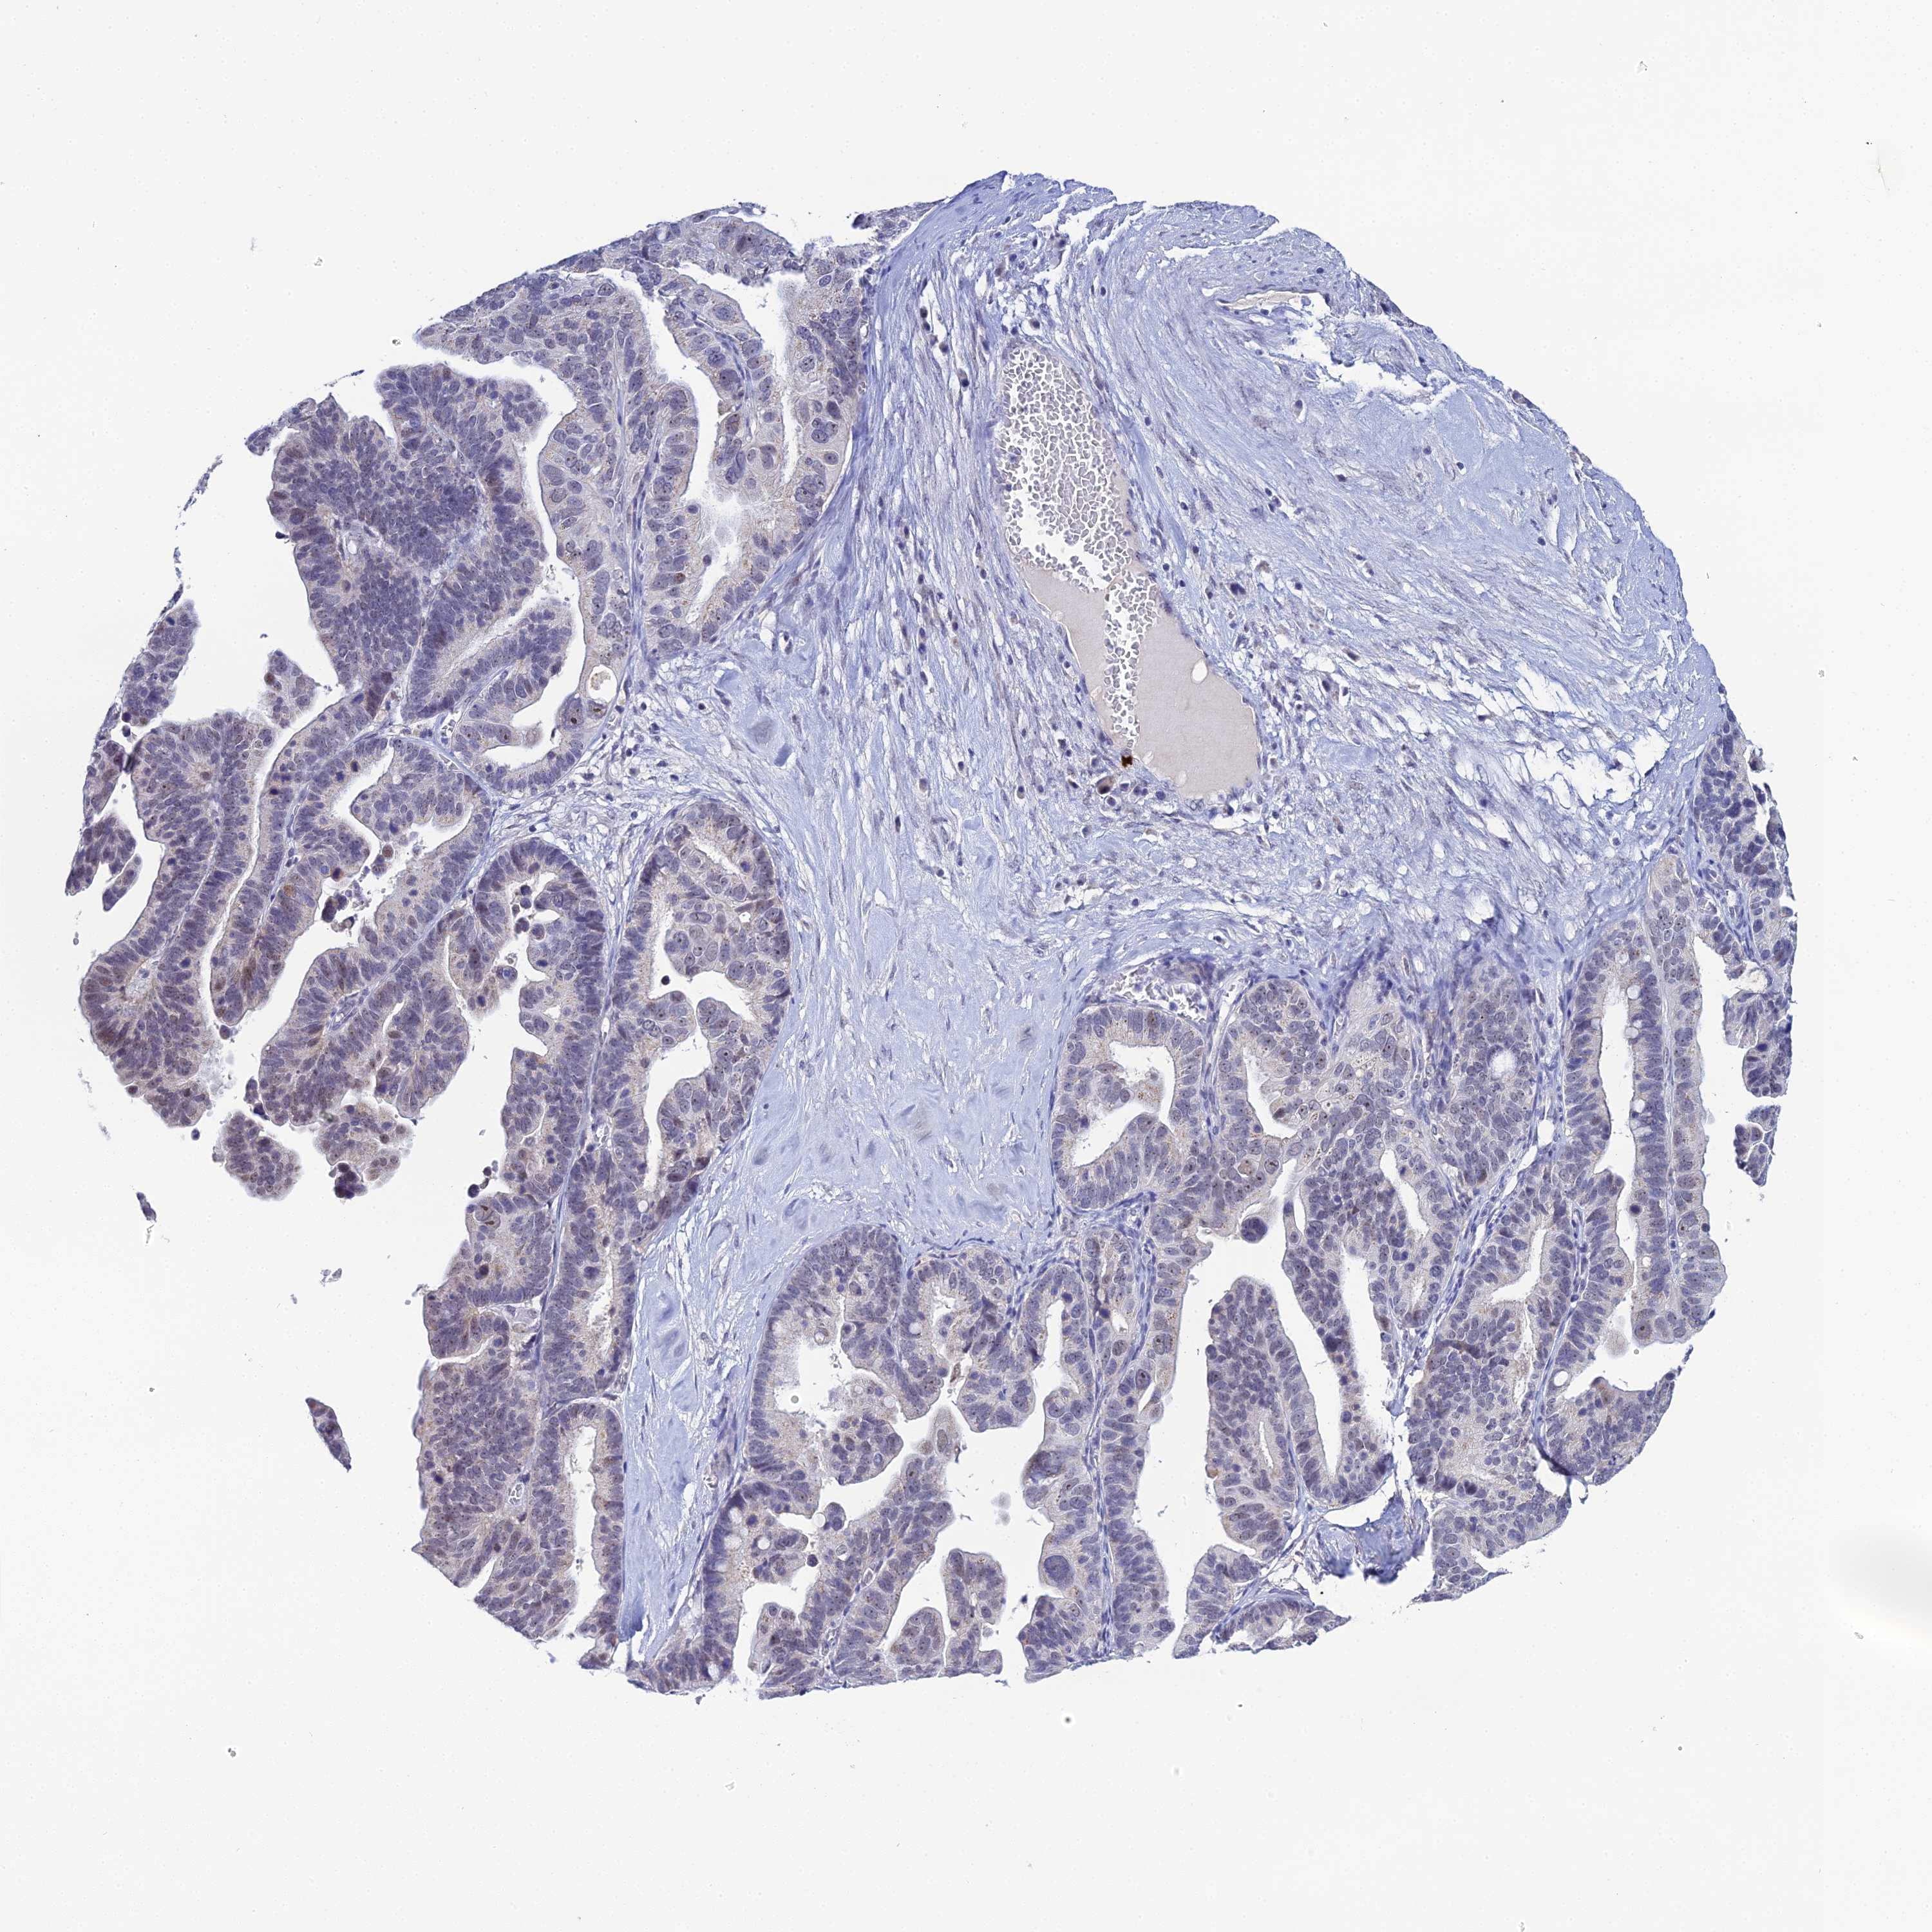

OVARIAN CANCER - Protein expressioni

A mouse-over function shows sample information and annotation data. Click on an image to view it in a full screen mode. Samples can be filtered based on level of antibody staining by selecting one or several of the following categories: high, medium, low and not detected. The assay and annotation is described here.

Note that samples used for immunohistochemistry by the Human Protein Atlas do not correspond to samples in the TCGA dataset.

Antibody stainingi

Antibody staining in the annotated cell types in the current human tissue is reported as not detected, low, medium, or high, based on conventional immunohistochemistry profiling in selected tissues. This score is based on the combination of the staining intensity and fraction of stained cells.

Each image is clickable and will lead to virtual microscopy that enables deeper exploration of all samples and also displays staining intensity scores, fraction scores and subcellular localization as well as patient and tissue information for each sample.

Antibody HPA045188

Staining

High

Medium

Low

Not detected

Intensity

Strong

Moderate

Weak

Negative

Quantity

>75%

75%-25%

<25%

None

Location

Nuclear

Cytoplasmic/membranous

Cytoplasmic/membranous,nuclear

Cystadenocarcinoma, serous, NOS

Carcinoma, endometroid

Cystadenocarcinoma, mucinous, NOS

Carcinoma, NOS